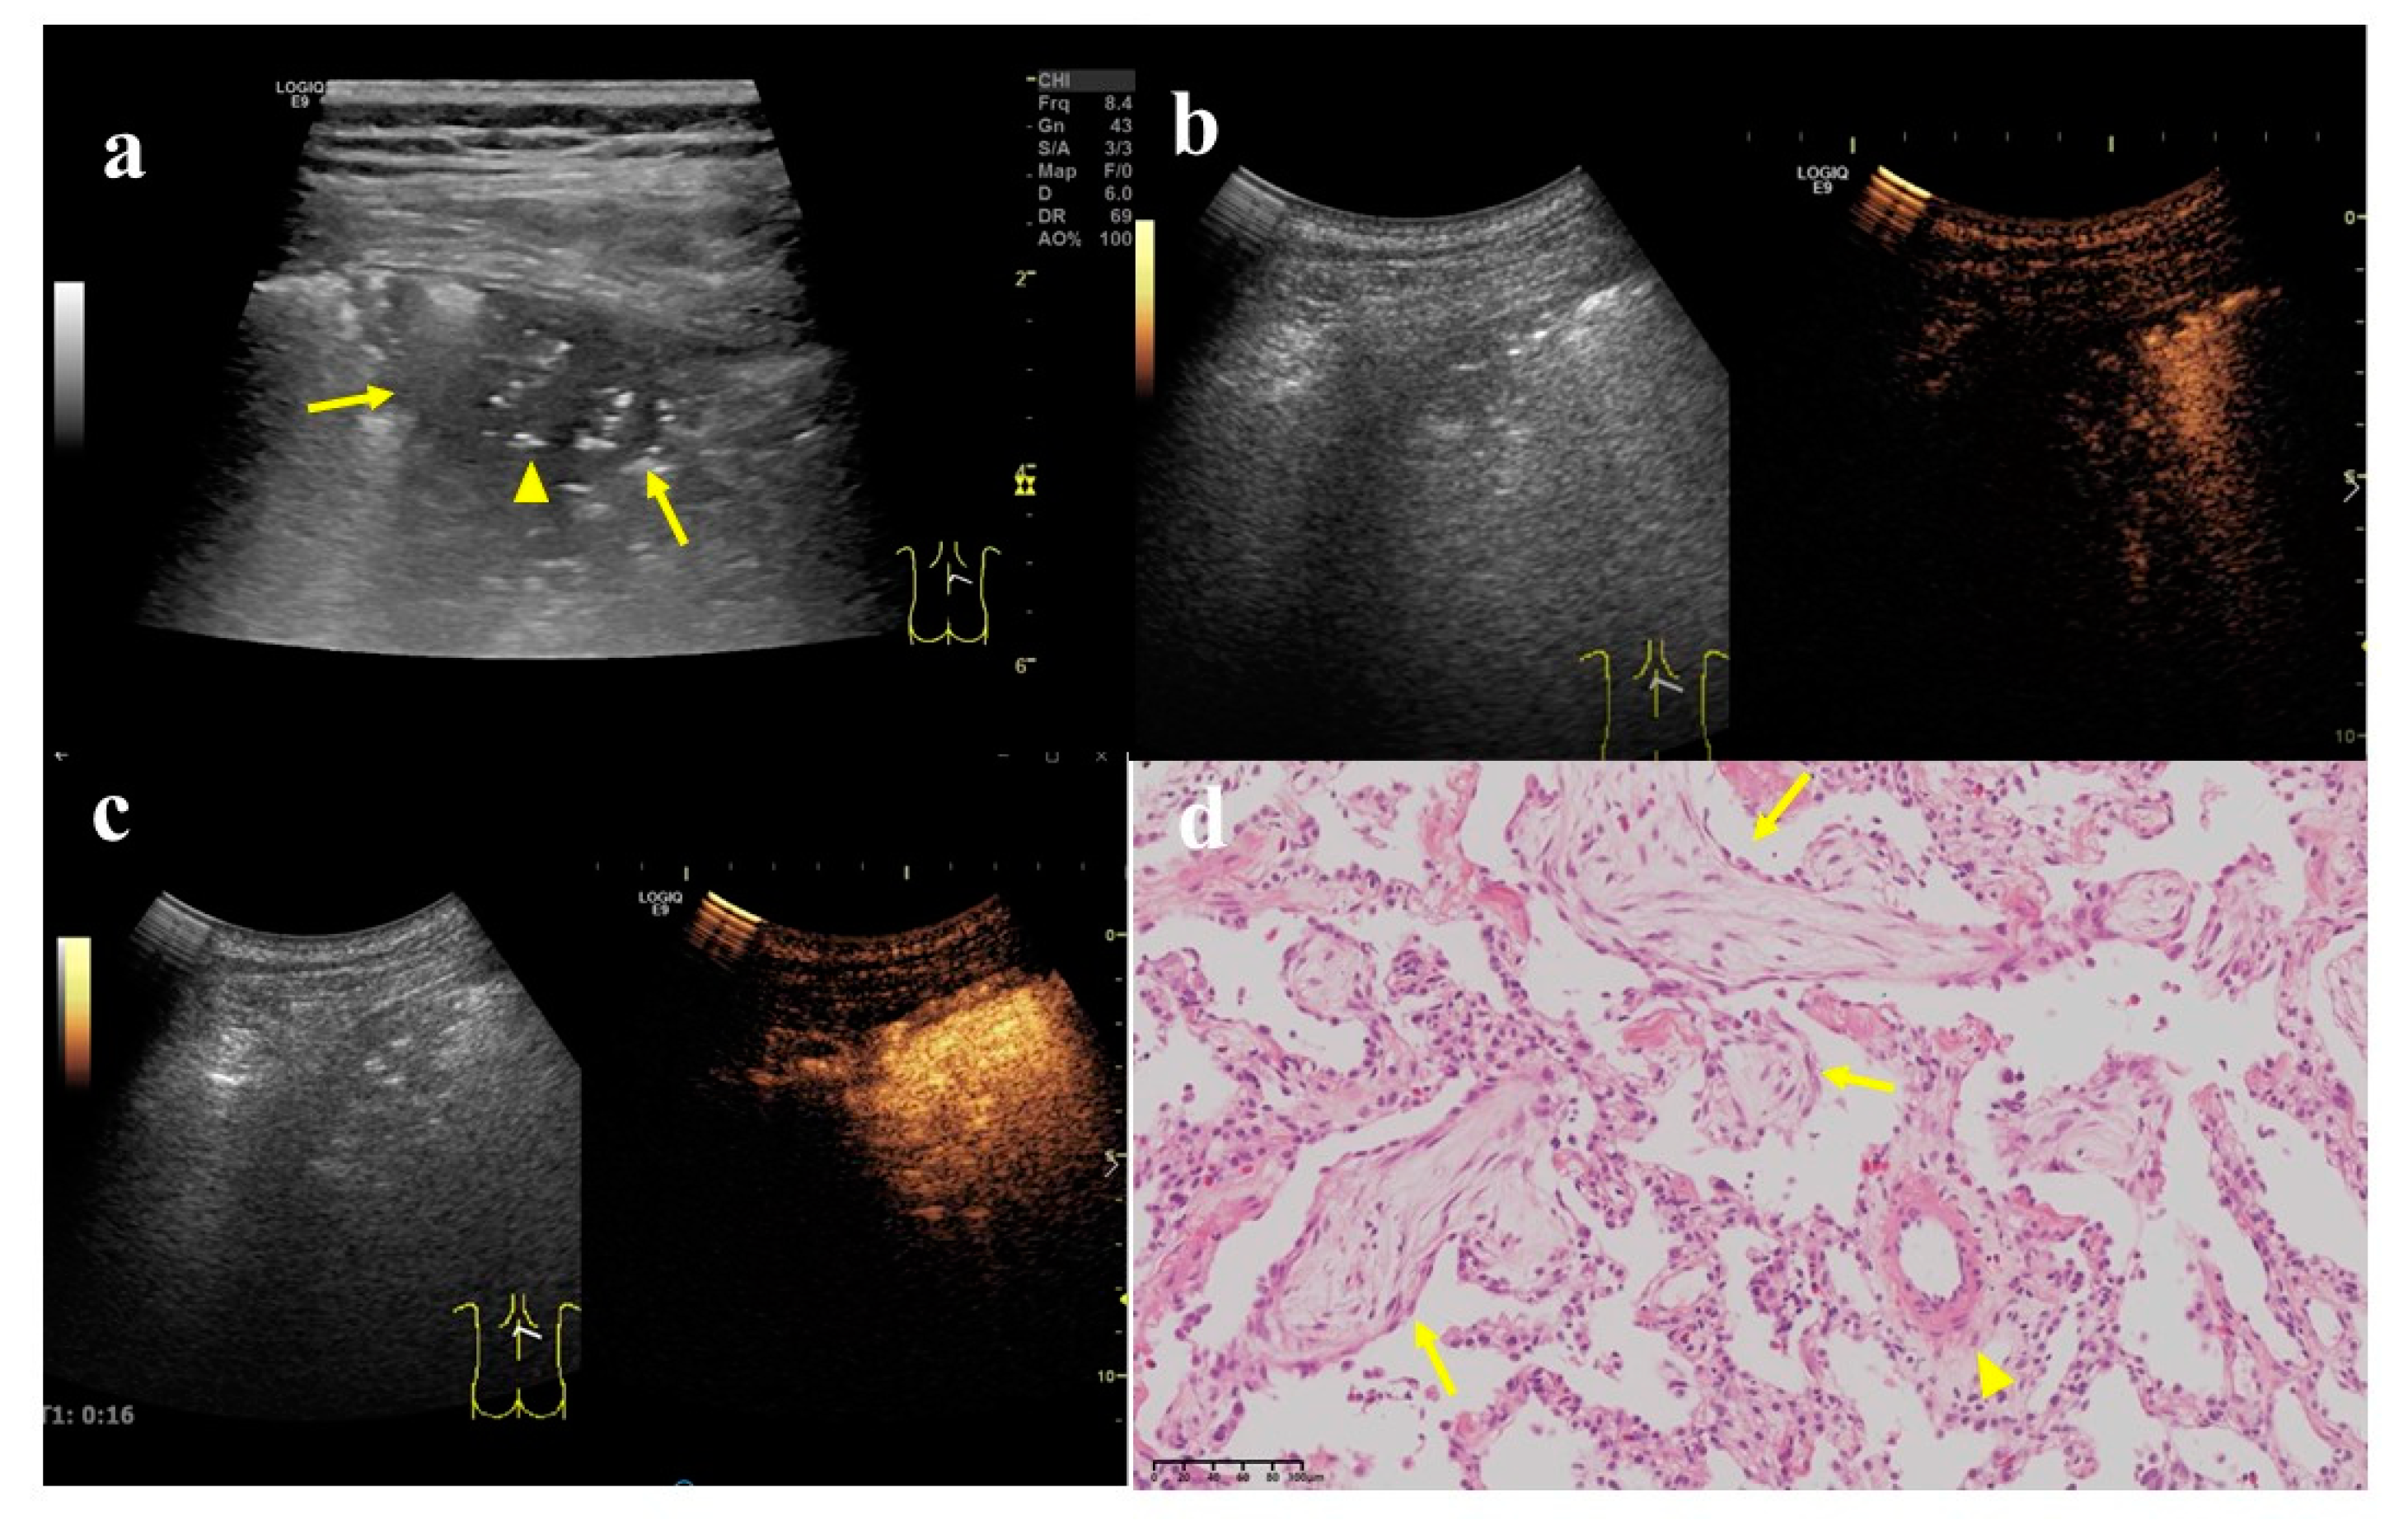

Figure 5. A 58-year-old male with a lesion occupying the deep space in the lower corner of the right shoulder armor. (a) Two-dimensional ultrasound showed a hypoechoic nodule, size 5.5 × 4.5 cm (arrow). At least one angle (between lesion border and thoracic wall) was obtuse. (b) Contrast-enhanced ultrasound showed that the enhancement time of lung tissue was 10 s and that of nodule was 14 s. (c) The enhancement began from the periphery to the center. The enhancement reached the peak in 30 s, and the enhancement degree was obviously uneven. (d) Pathologic evaluations revealed lung adenocarcinoma, mainly solid and acinar (×200).